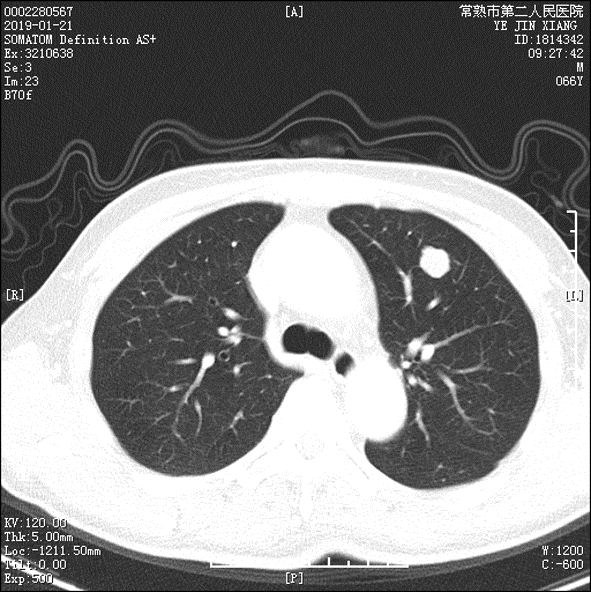

2019-1-21评估肺部转移进展,2019-2-23起予FOLFIRI化疗+贝伐单抗靶向治疗5次,末次化疗2019.4.20。

2019-07-16口服瑞格菲尼120mg qd,复查CT:双肺转移灶较前明显缩小。

2019-7-8: